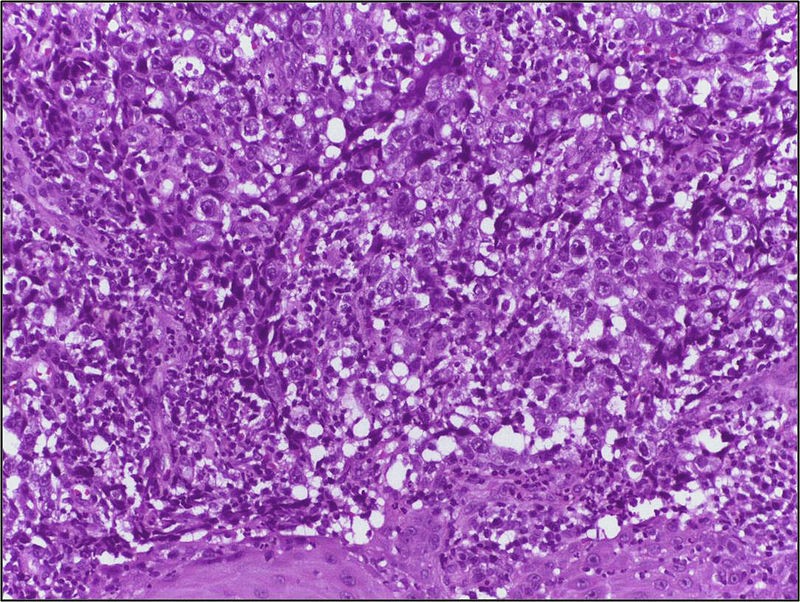

Las células del carcinoma de células claras muestran un citoplasma óptimamente vacío y una membrana citoplásmica muy bien definida (fig 8) En ocasiones las células muestran citoplasmas débilmente eosinófilos en torno al núcleo (fig 9), circunstancia observada en casos de alto grado nuclear. Definición El Carcinoma de Células Acinares es un tipo de adenocarcinoma, tumor maligno de las glándulas salivales, formado por células acinares claras que describen un patrón sólido o folicular, con escaso estroma visible Las células acinares pueden ser mucosas, serosas o ambas A veces son bilaterales y multicéntricos Sinónimos El Carcinoma de células Acinares también es. Carcinoma de células basales de histología no habitual a propósito de 4 casos Adrián P RodríguezCaulo, Katherine M GallardoRodríguez, Álvaro GutiérrezDomingo, Ana D Lozano Salazar.

Existen 3 tipos de cáncer de ovario Carcinoma epitelial representa el 8590% de los canceres de ovario Se desarrolla a partir de las células de la capa externa del ovario Son más frecuentes a partir de los 50 años Tumores de células germinales Se desarrolla en las células que generan los óvulos Representan un 10% de los casos y. El carcinoma de células claras muestra una histología altamente característica Las células del carcinoma de células claras muestran un citoplasma óptimamente vacío y una membrana citoplásmica muy bien definida. (nivel de evidencia 2a), enfermedad de Von Hippel Lindau, carcinoma papilar renal hereditario y otros tumores hereditarios (carcinoma renal familiar asociado a síndrome de BirtHoggDubé y leiomiomatosis hereditaria) Los tipos histológicos mas frecuentes son de células claras en 80 a 90%, papilar 15% cromófobo 45%, y.

HIsTOLOGIA La piel consiste en epidermis, dermis e hipodermis La epidermis consiste en un epitelio plano queratinizado estratificado, contiene cuatro tipos de células diferentes los queratinocitos, células de Merkel, melanocitos y células de Langerhans Hasta el 90% de la epidermis está constituida. Histologia O carcinoma de células escamosas surge da multiplicação descontrolada de células do epitélio e podem conter queratina e redes de filamentos ou desmossomos Existem 6 subtipos Adenoide, basaloide, células claras, células espinosas, células em anel de sinete e pleomórfico. Figura 1 Histologia dos subtipos histológicos mais comuns A CCR de células claras – células com citoplasma amplo e rico em lipídios, conferindo nome à neoplasia B CCR papilífero tipo 1 – células basófilas, pequenas, com citoplasma escasso, organizadas em arranjo fusiforme, dispostas numa camada única ao redor da membrana basal.

(nivel de evidencia 2a), enfermedad de Von Hippel Lindau, carcinoma papilar renal hereditario y otros tumores hereditarios (carcinoma renal familiar asociado a síndrome de BirtHoggDubé y leiomiomatosis hereditaria) Los tipos histológicos mas frecuentes son de células claras en 80 a 90%, papilar 15% cromófobo 45%, y. Histopatología Presenta células claras llenas de glucógeno que se proyectan individualmente en lúmenes y espacios papilares A diferencia del adenocarcinoma endometroide, el adenocarcinoma de células claras contiene grandes núcleos, altamente pleomórficos, a menudo con formas extrañas y multinucleadas. CARCINOMA ODONTOGÉNICO DE CELULAS CLARAS ESTUDIO CLÍNICO, RADIOLÓGICO Y PATOLÓGICO DE UN CASO Dr Reynaldo FalcónEscobedo*, Dra Rosaura Rodríguez Flores** * Profesor Titular de la Cátedra de Anatomía Patológica, Facultad de Medicina, Universidad Autónoma de San Luis Potosí.

Histologia Células Claras – Ilustrações As células claras, representam 75% dos casos, tendem a ter origem no túbulo proximal e apresentam tumores celulares invulgarmente claros pelo citoplasma rico em glicogênio e rico em lipídios Geralmente é o tipo de câncer renal com modificação genética, geralmente uma exclusão no cromossomo 3. En esta ocasión presentamos un caso de carcinoma de células renales típico, con su correlación de imagen e histología RESUmEn CLÍnICO Paciente masculino de 53 años de edad que acude al servicio de Urología del Hospital General de Culiacán, por presentar dolor en fosa iliaca derecha de 7 días de evolución,. Carcinoma combinado de células pequeñas;.

CARCINOMA DE CÉLULAS CLARAS Esta variante é a mais comum, representando entre 70% e 75% de todos os CCRs(3,7) Na grande maioria é do tipo com histologia de alto grau (15,16) Na tomografia computaTabela 1—Principais subtipos histológicos do CCR – epidemiologia, histologia e características de imagem. O carcinoma de células renais (CCR) é uma neoplasia que surge no parênquima renal/córtex O CCR de células claras representa a maioria (mais de 80%) das neoplasias renais primárias A incidência está aumentando junto com a migração de estádio para um diagnóstico em estádio mais inicial devido ao. Figura 1 Carcinoma de células claras de la glándula tiroides La microfotografía muestra células con núcleos pequeños, homogeneos con poca atipicidad y citoplasma claro HE X250 Figura 2 Microfotografía del carcinoma de células claras de la figura anterior Observese la penetración de la cápsula por las células neoplásicas.